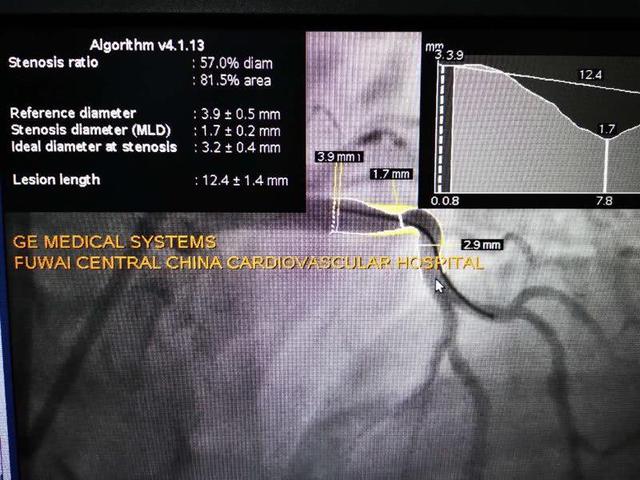

介入手术由高传玉团队的李牧蔚主任和饶立新主任医师开展。为了更好地了解患者血管狭窄的情况,以及判断支架具体施放的位置,在植入支架前,李牧蔚主任先用OCT(光学相干断层显像),在血管内部查看血栓和斑块的情况。

与传统的影像技术相比,高分辨率OCT可更加清晰地显示病变情况,从而更好地指导医生开展支架释放。在确定准确的狭窄位置后,李牧蔚主任操作导丝,将生物可吸收支架精准输送到病变部位,进行施放。

李牧蔚主任介绍说,为了更加准确地确定支架植入后的位置和效果,我们选择在手术后再次进行OCT检查,影像显示,没有支架的贴壁不良和明显的膨胀不良等情况,而且患者的血管基本恢复正常状态,没有出现不良反应,这就说明支架植入成功。